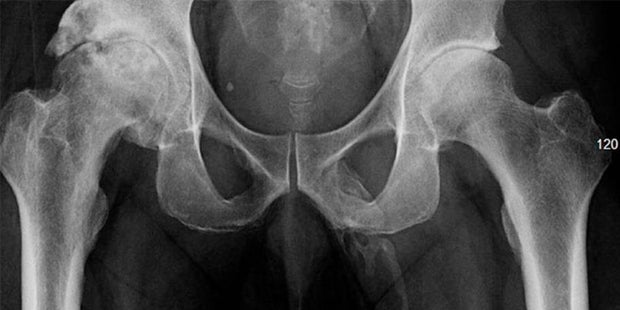

Die Ärzte machen ein Röntgen und machen darauf einen ungewöhnlichen Fund. Der 63-Jährige hat Knochengewebe an einer ungewöhnlichen Körperstelle: seinem Penis. Die Röntgenbilder zeigen, dass sich um den Penis des Mannes knochenähnliche Kalkablagerungen befinden. Der Patient gibt schließlich auch an, dass er Schmerzen in seinem besten Stück hat.

Ein solcher verknöcherter Penisschaft ist äußerst selten, bisher sind nur 40 Fälle bekannt. Verknöcherungen können zum Beispiel nach Operationen oder Verletzungen auftreten. Der 63-Jährige konnte nicht mehr untersucht werden. Er hat das Krankenhaus gegen den ärztlichen Rat verlassen.